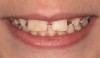

Using the wax-up as a guide, a composite restoration was fabricated for fused teeth Nos. 7 and 8 by roughening the affected area without pulpal exposure, etching the enamel, and applying primer and adhesive. Composite shade A1 was bonded to the mesial and distal surfaces, with gingival dark composite applied to the cervical “interproximal” region. The tooth was then carved to resemble two teeth, matching the width of the created tooth central to tooth No. 9 (Figure 4 and Figure 5). The patient and her family were very pleased with the result, and no postoperative sensitivity was reported.

Fig 4 and Fig 5. The fused tooth was carved to resemble two teeth, matching the width of the created tooth central to tooth No. 9.